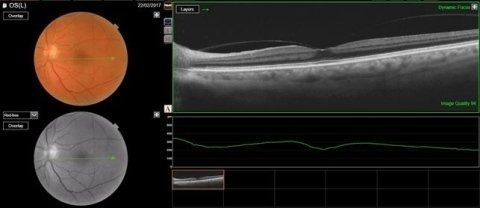

• OCT maculare, per indagare la morfologia della retina maculare e l'andamento delle diverse maculopatie fra cui l’AMD: la maculopatia correlata all’età

• OCT papillare, utile per valutare la morfologia delle fibre del nervo ottico soprattutto nella diagnosi del glaucoma

• Foto del fundus, ossia un’immagine del fondo oculare , della retina e del nervo ottico

• Pachimetria, esame che serve a interpretare nel modo più corretto i valori della pressione oculare

• Analisi della cornea, per studiare le diverse patologie corneali

• Esame della camera anteriore, per valutare eventuali rischi di glaucoma acuto ed eventuali indicazioni all'iridotomia

La tomografia ottica computerizzata (OCT) è un esame che rappresenta un passo fondamentale nella diagnostica oculistica avanzata. Questo innovativo metodo diagnostico è completamente non invasivo e offre la possibilità, senza causare alcun dolore al paziente, di ottenere scansioni straordinariamente precise e ad alta risoluzione della cornea e della retina. Grazie alla tecnologia all'avanguardia della OCT, effettuata presso lo studio oculistico della dottoressa Tormene, è possibile non solo monitorare la salute degli occhi, ma anche identificare con tempestività un ampio ventaglio di patologie corneali, retiniche e del nervo ottico. Questa precoce individuazione consente ai medici di intervenire in modo efficace, applicando la terapia più adatta alle specifiche esigenze del paziente, garantendo così una migliore prognosi e una maggiore qualità della vita visiva.